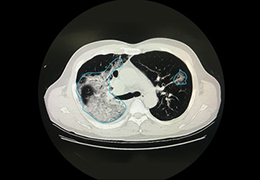

Eclipse 成像智能功能提供强大的处理能力和最佳质量的影像,同时减少质量错误并提高剂量效率。

凭借 AI、专有算法和先进的影像处理能力,提供出色的影像质量和无与伦比的诊断信心。

与标准影像处理相比,智能降噪功能可使客户降低辐射剂量,而不会损失影像质量。这在新生儿和儿科成像中尤其重要,在这种情况下以尽可能低的剂量成像至关重要。